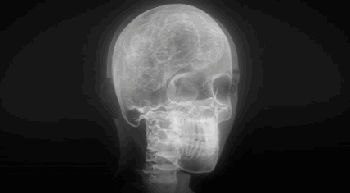

放射医学是医学的一个专门领域,它使用放射线照相术和其他技术产生诊断图像,这可能是X射线技术应用最广泛的地方。

借助计算机,人们可以把不同角度的X射线影像合成成三维图像,在医学上常用的电脑断层扫描(CT扫描)就是基于这一原理。

X射线应用于医学领域主要包括疾病诊断和治疗。

X射线应用于医学诊断,主要依据X射线的穿透作用、差别吸收、感光作用和荧光作用,也就是大家所“拍摄”的X光。

由于X射线穿过人体时,受到不同程度的吸收,如骨骼吸收的X射线量比肌肉吸收的量要多,那么通过人体后的X射线量就不一样,这样便携带了人体各部密度分布的信息,在荧光屏上或摄影胶片上引起的荧光作用或感光作用的强弱就有较大差别,因而在荧光屏上或摄影胶片上将显示出不同密度的阴影。

根据阴影浓淡的对比,结合临床表现、化验结果和病理诊断,即可判断人体某一部分是否正常。